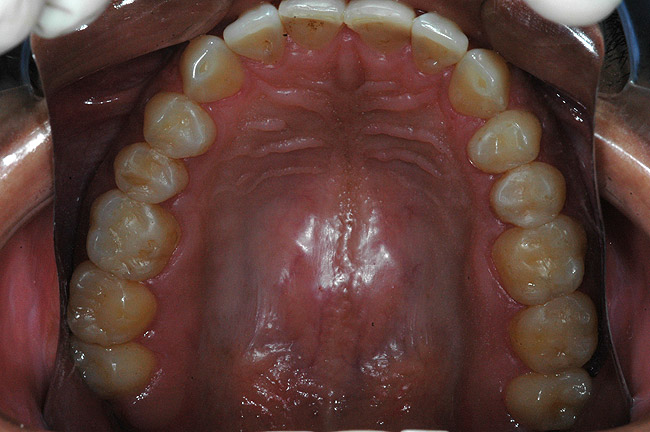

În cursul examinării clinice s-a notat o igienă orală satisfăcătoare. Pacientul prezenta coroziunea suprafeţelor ocluzale şi orale la dinţi maxilari şi mandibulari posteriori (fig. 1). Avea, de asemenea, arii expuse de ţesut dentinar (fig. 3) şi restaurări din amalgam compromise în lipsa sprijinului adecvat.

Întrucât pierderea suprafeţei dentare este o stare multifactorială, planul de tratament dentar trebuie să includă terapia medicală în scopul prevenirii leziunilor ulterioare, implicând practicieni din alte sfere medicale pentru stabilirea diagnosticului definitiv. În cazul de faţă, aspectul clinic al leziunilor a sugerat diagnosticul: suprafaţa ocluzală a dinţilor posteriori prezenta arii decupate sau depresiuni, cu aspect în formă de lingură, cauzat de eroziune.1,12